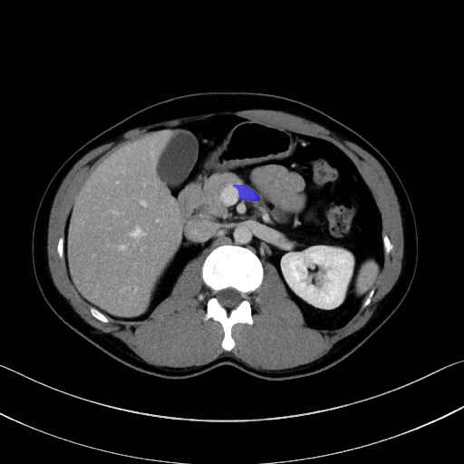

脾静脈の画像解剖

■起始:脾門で脾静脈枝が合流して本幹を形成。

■走行:膵体尾部の後面溝を右走し、膵頸部の後方で上腸間膜静脈(SMV)と合流して門脈を形成。

■主な流入枝:短胃静脈・左胃大網静脈・膵静脈、そして下腸間膜静脈(IMV)(変異あり)。